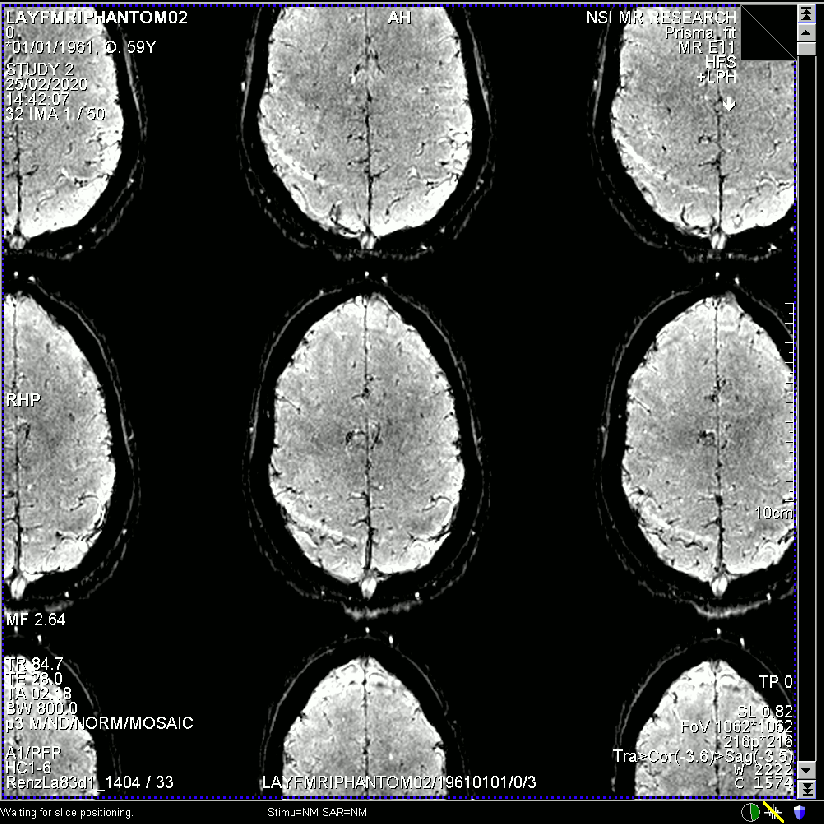

Example from another participant.

Data are taken from this study.

- Raw single time point image quality of the same dataset reconstructed with different regularization factors.